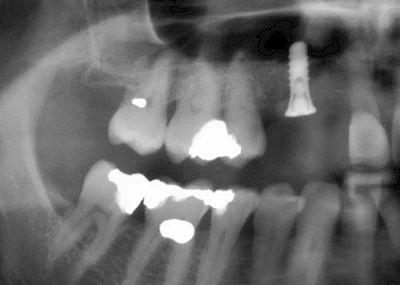

Implantatplanung

Damit Implantate an der richtigen Stelle im Kieferknochen platziert werden könen, gibt es heute vielfältige Möglichkeiten der Planung. In vielen Situationen kann die Erfahrung des Zahnarztes ausreichend sein.

Nicht selten ist jedoch auch eine technisch aufwändigere Vermessung im Vorfeld sinnvoll, z. B.:

- Wenn sich der Kieferknochen abgebaut hat

- Wenn der Nervverlauf im Unterkiefer beachtet werden muss

- Wenn die Ausdehung der Kieferhöhle im Oberkiefer beachtet werden muss

- Wenn wenige Restzähne keine gute Orientierung erlauben

In diesen Fällen kann die Planung mittels verschieden aufwendiger Röntgen-Techniken (Übersichtsaufnahme, DVT) ggf. unter Zuhilfenahme speziell angefertigter Planungsschablonen sinnvoll sein.